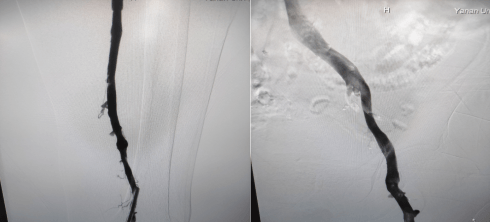

術中造影左下肢股靜脈、腘靜脈大量血栓形成